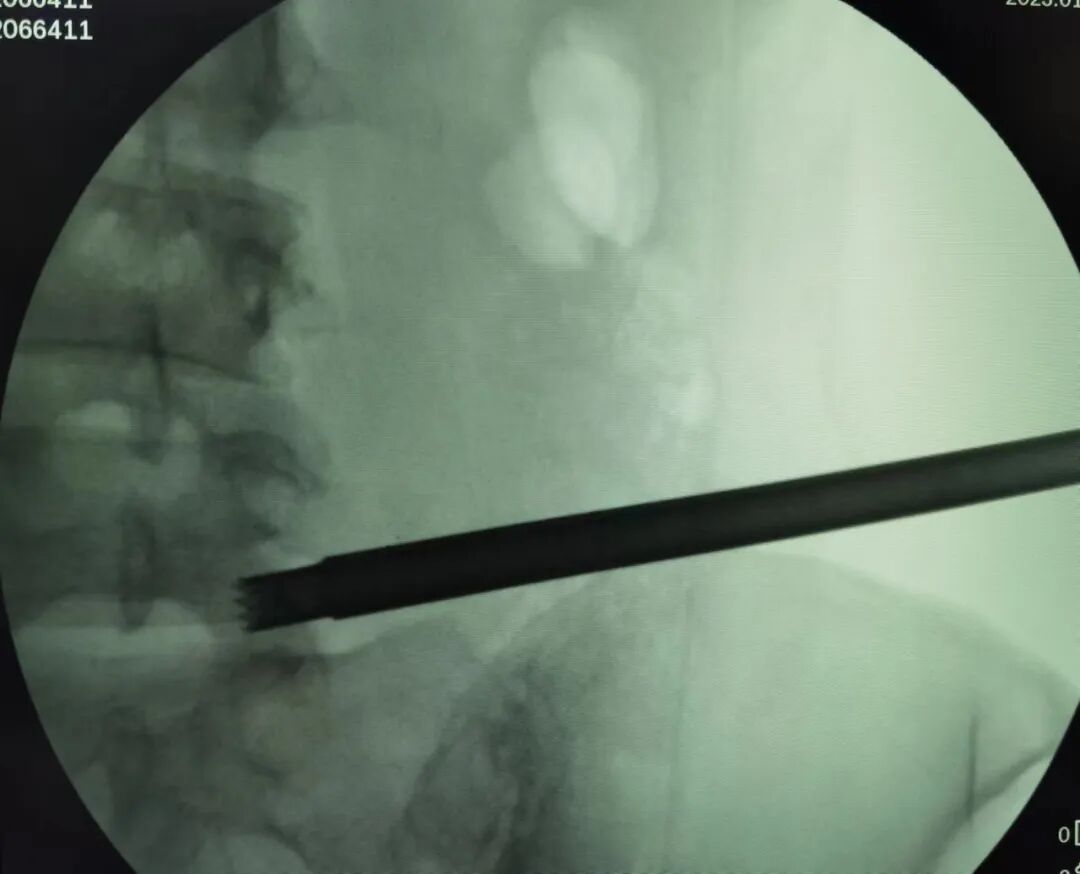

第一步:标记

通过 C 臂机透视以克氏针确定椎间盘突出节段并标记穿刺方向。穿刺方向由头外侧斜向尾内侧,在正(前后)位上 L5/S1 与上关节突(superior articular processes,SAP)呈约 40~50°,L4/L5 和 L3/L4 则分别呈约 30~40°和 25~30°。

此外,也可作一条连接 SAP 尖和上终板中点的直线。

克氏针标记 L5/S1 节段的 C 臂透视影像